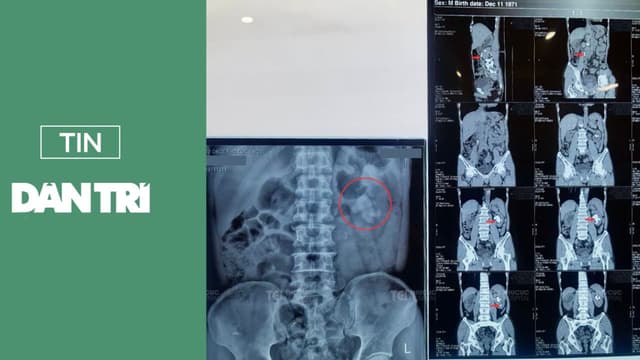

Báo điện tử Dân Trí đưa tin về bài viết “Thách thức tán sỏi san hô khổng lồ cho bệnh nhân hậu tai biến” ngày 27/03/2025. Để cập nhật thông tin tới khách hàng, chúng tôi sẽ trích nội dung từ Báo Dân Trí để cung cấp tới bạn đọc. Trích dẫn toàn bộ nội […]